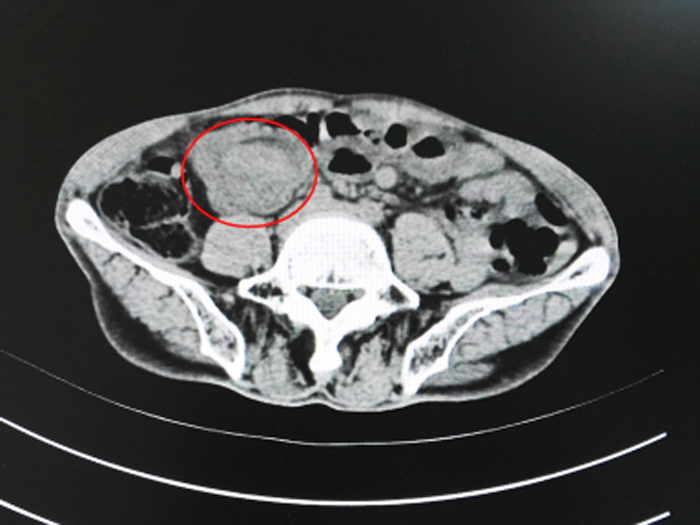

只是在面对CT报告时,他却开始质疑起来了:我来看“拉肚子”,你告诉我是肿瘤?搞错了吧?

下图便是大叔的腹部CT截图,可以清晰看见占位。

我也希望这只是一场美丽的误会,而不是一场悲剧的开始。